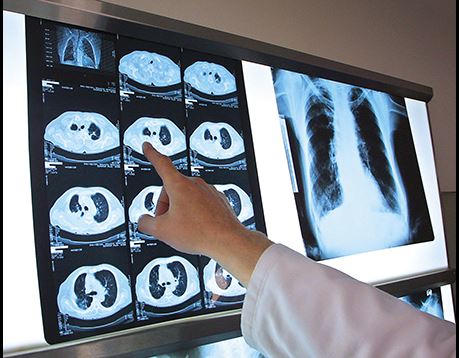

From broken bones to blocked intestines, Rad Techs see it all. Radiologic Technologists capture images of human anatomy using digital imaging, x-ray film or video, which are then used by radiologists or other medical specialists to identify and diagnose conditions inside the body. OCC offers a two-year associate degree program that is accredited by the Joint Review Committee on Education in Radiologic Technology and approved by the California Department of Public Health. Graduates are eligible to sit for the California state Certified Radiologic Technologists (C.R.T) exam. If you picture yourself working as a vital part of a health care team, OCC's Radiologic Technology program can help you get there. Read on to learn more.

Prepare for a career as a radiologic technologist, capturing images of human anatomy using digital, x-ray film, or video for diagnostic use by a radiologist or other medical specialist. After completing this program, you will be eligible for the American Registry of Radiologist Technologists certification exam and for the state Certified Radiologic Technologist exam. In order to practice in California, you also must apply for certification by the Department of Health Services in Sacramento. Or take your education further and enroll in a related bachelor's degree program at California State University, Northridge.